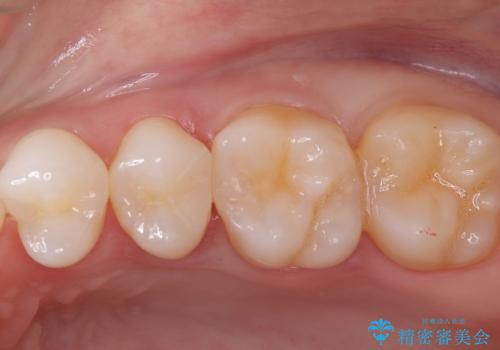

銀歯の下に虫歯 〈オールセラミッククラウン〉

- 初診時に金属の下に虫歯があることを指摘しました。もともとの詰め物の形と虫歯の大きさから被せものでの治療となりました。見た目、材質の説明をし、セラミッククラウンでの修復となりました。

メタルインレーが入っていたこと、う蝕が大きかったこと、頬側にHysに対してのCRがあったことを踏まえてクラウンでの修復を選択しました。